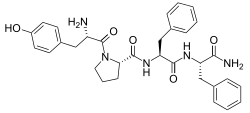

Opioid peptides

Endomorphins

Endorphins

Structures

Enkephalins

Structures

| Enkephalins | ||||

|---|---|---|---|---|

DAMGO DAMGO |

||||

Propeptides

Others / unknown

- Adrenorphin

- Amidorphin

- Biphalin

- Casokefamide

- Casomorphins

- Cytochrophin-4

- DALDA (Tyr-D-Arg-Phe-Lys-NH2)

- Deltorphin I

- Deltorphin II

- Deprolorphin

- Dermorphin

- DPDPE

- Frakefamide

- Gliadorphin

- Gluten exorphins

- Hemorphin-4

- Metkefamide

- Morphiceptin

- Nociceptin

- Octreotide

- Opiorphin

- Rubiscolin

- Soymorphins

- Spinorphin

- TRIMU 5

- Tynorphin

- Valorphin

- Zyklophin

Structures

| Other or unknown opioid peptides | ||||

|---|---|---|---|---|

Adrenorphin Adrenorphin |

Amidorphin Amidorphin |

Casomorphin Casomorphin |

DALDA DALDA |

|

DPDPE DPDPE |

Endomorphin-1 Endomorphin-1 Endomorphin-2 Endomorphin-2 |

Gliadorphin Gliadorphin |

Morphiceptin Morphiceptin | |

Nociceptin Nociceptin |

Octreotide Octreotide |

Opiorphin Opiorphin |

Rubiscolin Rubiscolin |

TRIMU 5 TRIMU 5 |